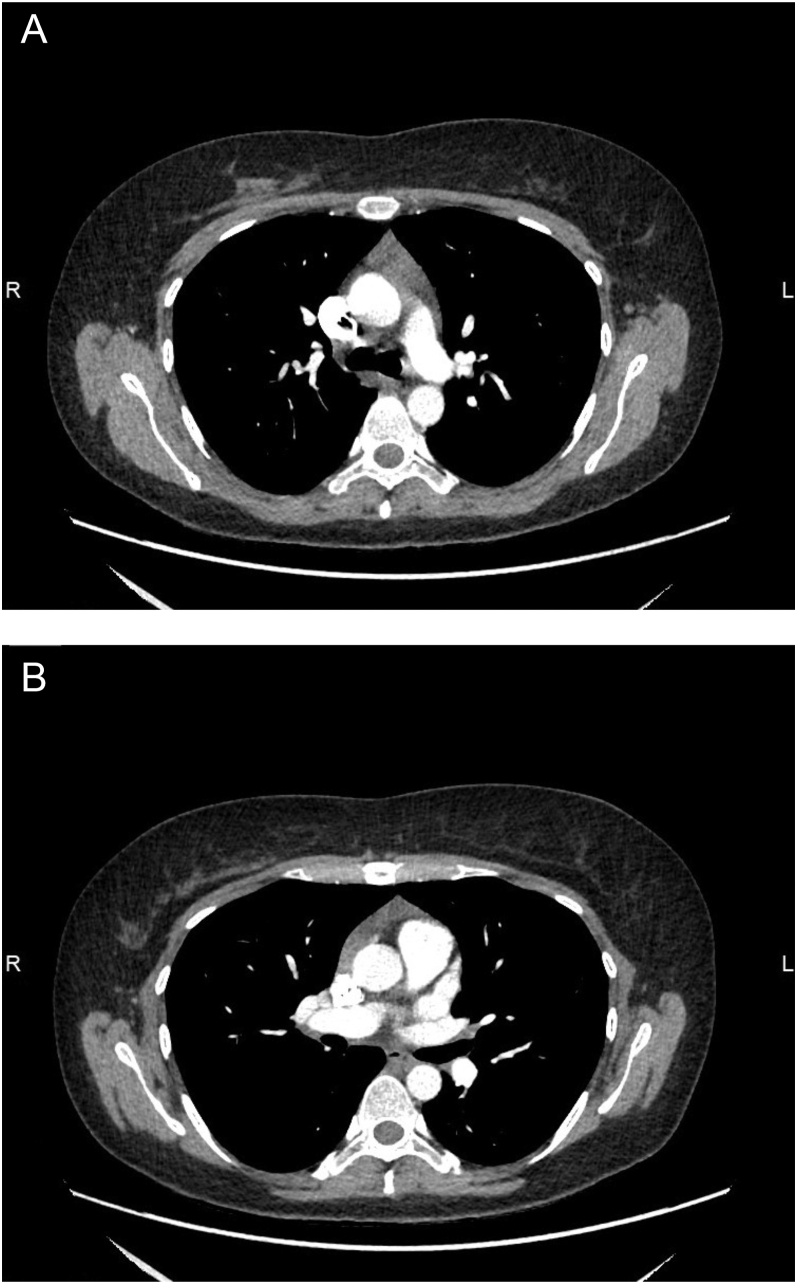

Summary: Thymic hyperplasia in Graves' disease is rarely identified due to the absence of routine imaging, but not uncommonly present. It is usually seen when imaging is performed for other reasons. Despite thymic hyperplasia becoming a more commonly identified occurrence, follow-up imaging scans and multi-disciplinary team (MDT) approach are still recommended to distinguish this benign transformation from more significant differentials. These steps can lead to distress in patients. Therefore, clinicians and radiologists being aware of this correlation between thymic hyperplasia and Graves' disease can add reassurances about the most likely diagnosis whilst the patient is undergoing limited further investigation to rule out differentials and subsequently, avoid unnecessary intervention. Here, we report a case of Graves' disease with thymic hyperplasia in a young woman who initially presented with non-specific eye symptoms and incidental mediastinal mass, in which involvement of multiple speciality teams was important to rule out thymoma and myasthenia gravis (MG).

Learning points: Although Graves' disease with thymic hyperplasia is not uncommon, it is sometimes difficult to diagnose with one imaging scan due to the overlap of radiological characteristics of other important differentials; an MDT discussion and further imaging scans are needed to confirm the diagnosis in some cases. Getting MDT involvement early would quickly assist in ruling out more significant differentials and avoid unnecessary surgical intervention by concluding thymic hyperplasia. Clinicians having knowledge on the relation between Graves' disease and thymic hyperplasia may reassure the patient by explaining the possible resolution with treatment, while awaiting further MDT discussion. To rule out ocular MG in Graves' disease patients, additional investigations and neurology referral are often required as the serum antibody tests are less sensitive in ocular MG than generalised MG.